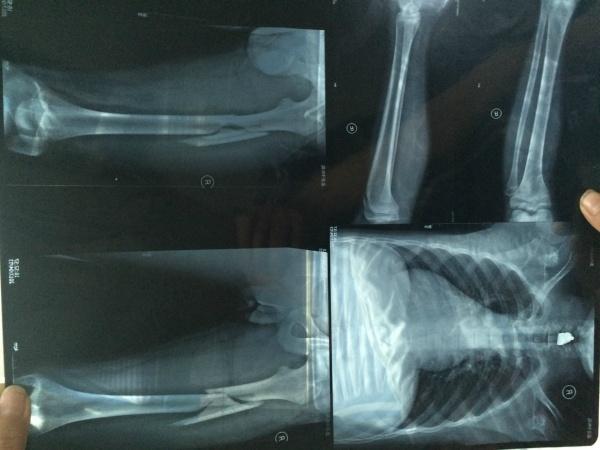

• 骨折

628健康網為您分享有關骨折的癥狀,骨折的治療方法,骨折的預防知識,骨折的癥狀圖片,骨折吃什么藥,骨折怎么治療,骨折患者食...